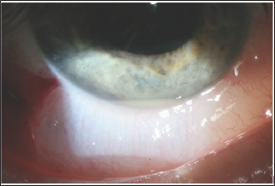

A 54 year-old Caucasian male with hypertension, diabetes mellitus, hyperlipidemia, and prostate cancer and no ocular history presented to the emergency room with dull abdominal pain. He was found to have an ST-elevation myocardial infarction (STEMI) and underwent urgent coronary stenting. The following day he was septic with Methicillin-sensitive staph aureus (MSSA) bacteremia and started on appropriate intravenous antibiotics. Urine cultures and echocardiogram were unremarkable. Two days later he developed blurry vision in the left eye with a visual acuity (VA) of 20/300, and he was found to have a hypopyon, anterior chamber inflammation, and vitreous membranes all while the right eye was unremarkable. He was diagnosed with endophthalmitis of the left eye and due to the rapid nature of the findings he underwent a pars planavitrectomy with intravitrealvancomycin and amikacin (Figure 1).

Figure 1: Hypopyon of the left eye.